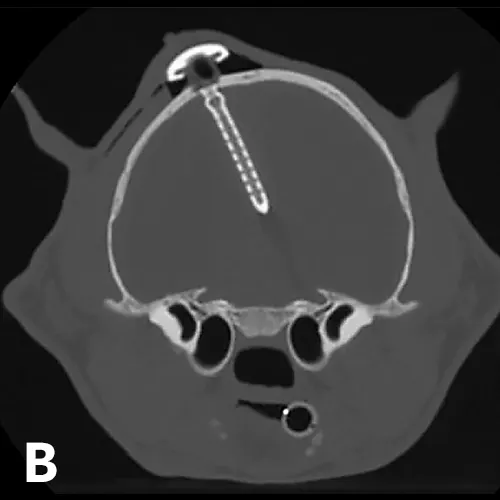

X-ray and CT images of a cat showing radiopaque ventriculoperitoneal shunt in place within skull.

FIGURE 5

(A) Postoperative lateral radiograph and (B) transverse CT image showing a ventriculoperitoneal shunt placed in a cat. Although the well was not flush with the skull, the shunt appeared stable after the sutures were tightened. The cat did well after surgery. Images courtesy of Dr. Eric Glass, Red Bank Veterinary Hospital/Compassion First Pet Hospitals